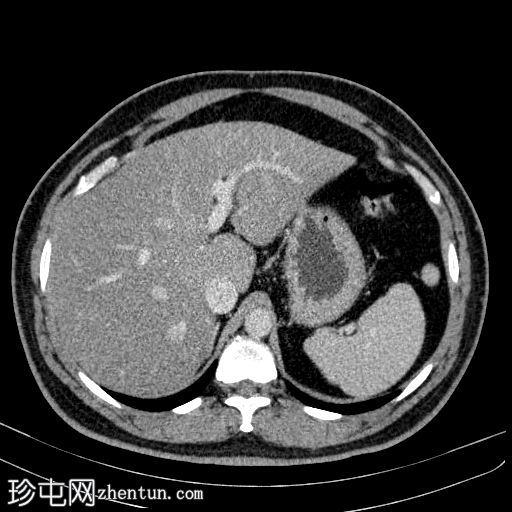

轴位增强扫描

门静脉期

在左侧输尿管膀胱连接处可见一枚24×15 mm的大膀胱结石。膀胱壁轻度弥漫性增厚,厚度约6 mm,提示膀胱炎。

可见多个副脾(脾小体),位于主脾实质的上方和下方,在影像学各期均表现出与脾脏相似的衰减值。

肝脏弥漫性脂肪浸润。